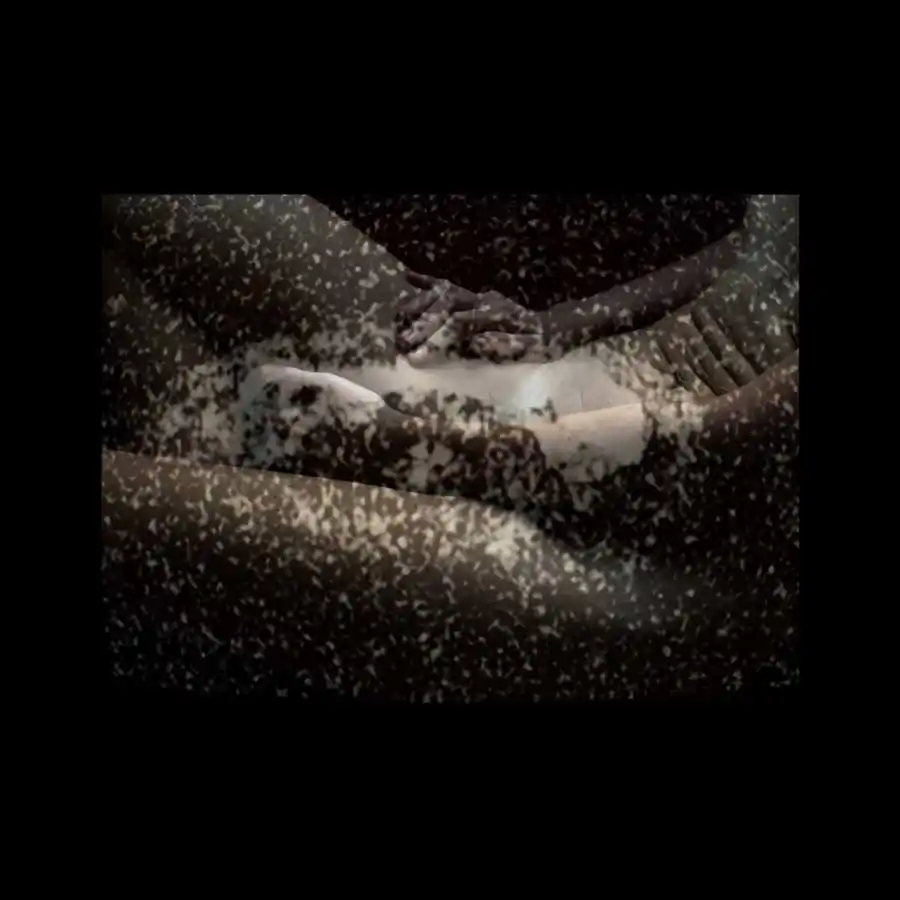

The project ‘Limits of existence’ are self-portraits compiled by the author with MRI scans. It is a case-record, in which the body appears as a subject to internal researches and the only way of communication with the outside world.

Working with the fear of physical existence termination, the author examines the physiological processes that occur during her illness with the threat of death, as the only real manifestation of life, as the limits of the possible. All thoughts, feelings and experiences, focused on physical sensations, force the author to reconsider the meaning of ‘Me’, ‘person’, ‘soul’; also the question of possibility for the spirit to overcome the boundaries of the body or expand them is raised. [Official Website]